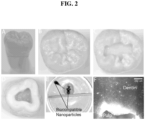

• the invention exploits dentinal tubules to deliver nanoparticles or nanoparticles loaded with medications and uses magnetic forces to transport the nanoparticles to the dentinal tubules ( FIG. 2 ).

• the teeth were sectioned horizontally at the level of the pulp chamber using a diamond disk ( FIG. 2D ; line in 2A).

• the teeth were suspended in saline, in a petri dish, and placed on top of a magnet.

• Nanoparticles 50 ⁇ L of 100, 300 and 500 nm hydrodynamic size, were placed in the cavity. The particles have a magnetic core that allows them to be steered, in this case pulling them to the magnet. After 30 minutes, nanoparticles can be seen in the petri dish under the teeth, an example is shown in Fig. 2E . Teeth were then sectioned longitudinally and examined under an epi-fluorescence microscope.